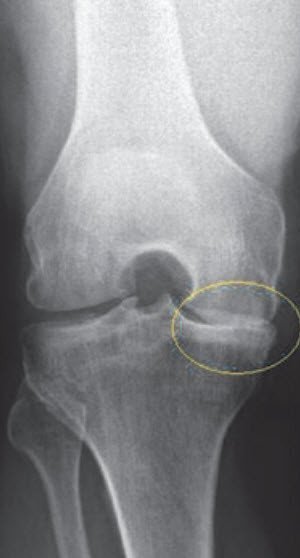

Osteoarthritis, a degenerative and mostly age-related wearing of the cartilage surfaces, causes inflammation and therefore pain in the knee. The bone structure is gradually damaged further and mobility severely restricted. Osteoarthritis cannot be healed and usually progresses until the knee joint is completely destroyed. Wear of the knee joint is the most common reason for knee joint replacement.

If only the kneecap or the inner or outer part of the knee joint is affected by wear, partial joint replacement (sled prosthesis/unicompartmental knee arthroplasty) may be performed. Important prerequisites for this indication are that the osteoarthritis is primarily limited to a single section of the knee joint and that the knee ligaments are still functional.